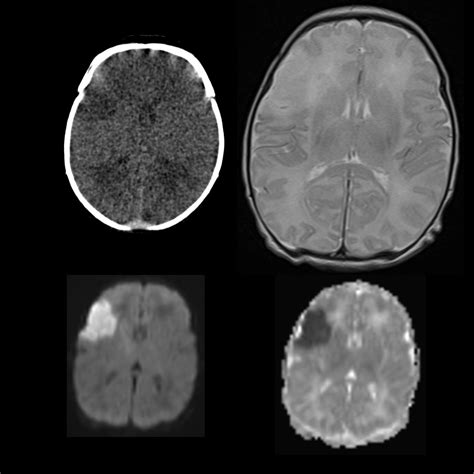

Computed Tomography (CT) scans are essential in the diagnosis of ischemic stroke. An Ischemic Stroke CT scan can quickly and accurately detect the presence of a stroke, differentiate it from other conditions, and guide treatment decisions. The scan uses X-rays to create detailed images of the brain, which can reveal:

• Non-contrast CT (NCCT): This is the most basic type of CT scan and is often the first test performed. It provides a clear view of the brain structures and can detect early signs of ischemia, such as the “dense artery sign,” which indicates a blood clot.

• CT Angiography (CTA): This type of scan uses contrast dye to visualize the blood vessels in the brain. It can identify the location and extent of a blood clot and assess the condition of the blood vessels.

• CT Perfusion (CTP): This scan measures blood flow to different areas of the brain. It can help determine the extent of brain tissue that is at risk of dying (the penumbra) and guide decisions about thrombolytic therapy.

Interpreting the results of an Ischemic Stroke CT scan requires expertise and experience. Radiologists and neurologists work together to analyze the images and make a diagnosis. Key findings that may be observed include:

• Early ischemic changes: These can appear as areas of low density (hypodensity) in the brain tissue, indicating reduced blood flow.

• Hyperdense artery sign: This is a bright appearance of an artery on a non-contrast CT scan, suggesting the presence of a blood clot.

• Mass effect: Swelling or compression of brain tissue due to the stroke, which can be seen as a shift in the midline structures of the brain.